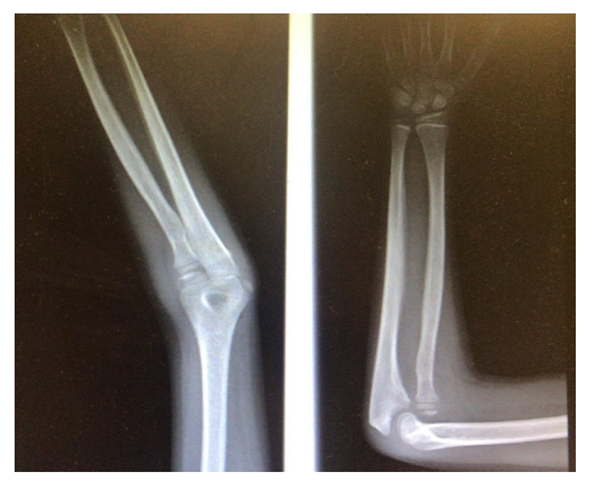

The first step concerns the conversion of tomographic images into a three-dimensional model. As mentioned, the images deduced from the CT are not always appropriately clear to allow the medical specialist to develop in detail the procedure to be performed before the operation, so the process is divided into three main phases in order to emphasize the exact region and create the 3D model, removing unnecessary anatomical parts. Computed tomography is converted to standard triangulation language (STL) to represent the examined anatomy in three dimensions, but the model is too heavy, computationally speaking, and is marked by a dense structure that must be optimized. To do that, MeshLab is used for the elimination of the inner material of no interest and the overlapped geometries, and MeshMixer for external surface and file format correction. The steps of this first part of the workflow are summarized below (in order: Figure 1 is the importation in InVesalius of the CT exam, Figure 2 is the processing to optimize the 3D surface obtained and Figure 3 is the correction of mesh errors.

Figure 2.

Removal of inner geometries.

Figure 3.

Detection of surface defects and Optimized three-dimensional models.